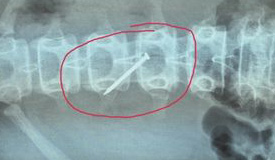

女孩吞下4厘米铁钉 家长:同学逼迫